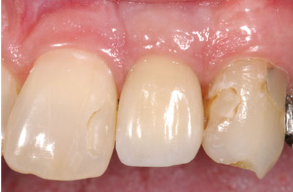

有时候医生也无法第一时间肉眼判断出来,而且现在假牙有的又做得那么逼真,可别忘了说~

种植牙除了前期找到专业医生来种,日常的维护和保养也是至关重要,这样才可以尽可能地延长第三副牙齿的使用寿命。